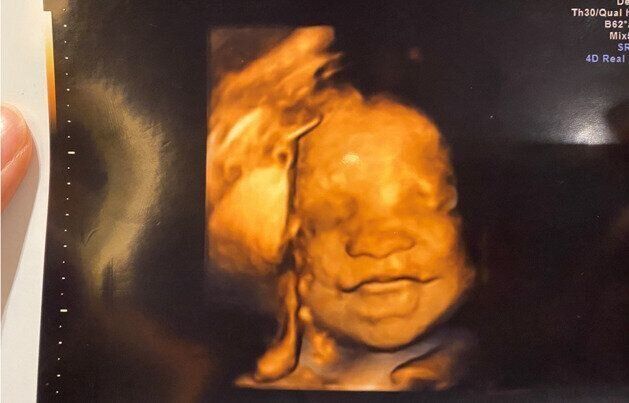

陣痛の兆候が見えたときに無料で利用できる「かるがも号」と呼ばれる24時間稼働の送迎車や、胎内の赤ちゃんの画像をビデオやDVDに録画する四次元超音波(4Dエコー)も妊婦さんにとっては嬉しいサービス。無痛分娩にも対応している。

四次元超音波( 4 Dエコー)によるおなかの中の赤ちゃんの映像をビデオやDVDに録画できる